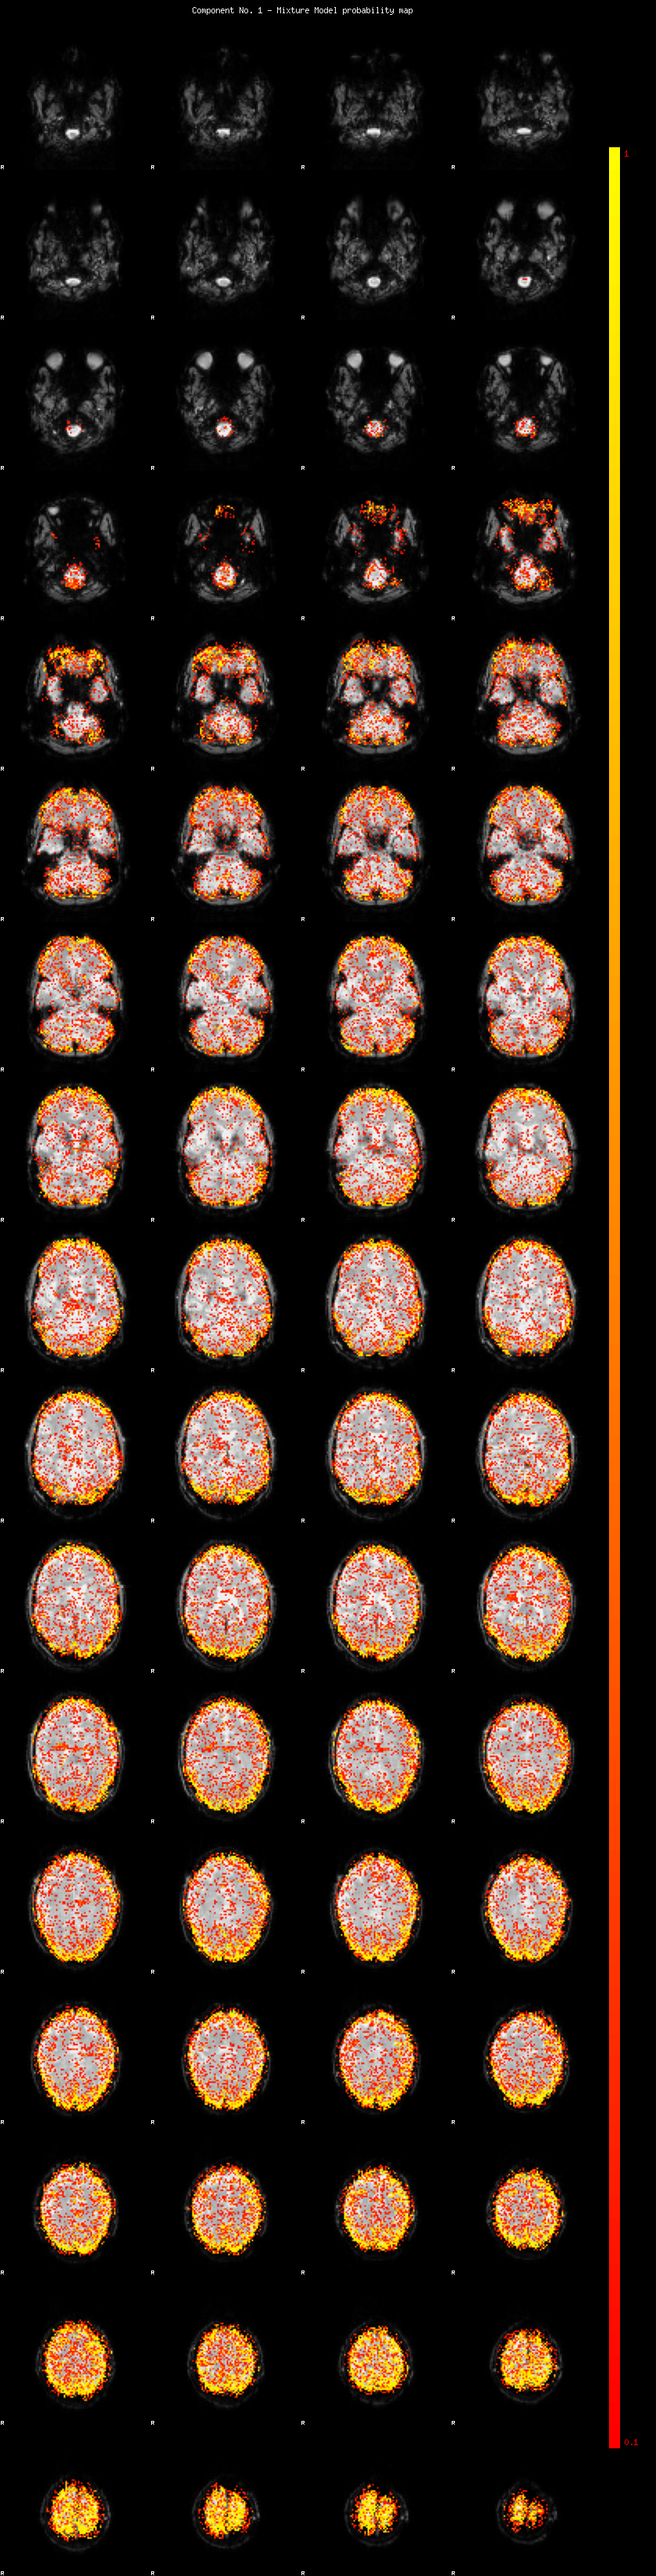

IC_1 Mixture Model fit

Means : -0.000000 3.499355 -2.888690

Vars : 1.000000 5.800963 3.292438

Prop. : 0.815749 0.099092 0.085159